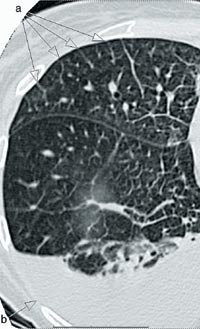

Ved innkomst ble det registrert en parasternal systolisk bilyd og en aksentuert annen hjertetone over pulmonalstedet. Elektrokardiografisk forelå det inkomplett høyre grenblokk, høyre akse og høyre ventrikkel-hypertrofi. Ekkokardiografi bekreftet funnene av hypertrofi, sammen med dilatasjon og hypokinesi av høyre ventrikkel, mens venstre ventrikkel var velfungerende. Pulmonal angiografi viste proksimalt dilaterte kar, men ingen tegn til tromboembolisme. Ved høyresidig hjertekateterisering var trykk i høyre atrium og i innkilt posisjon i a. pulmonalis normale, mens middelarterietrykk i a. pulmonalis var 44 mm Hg, minuttvolum var 2,8 l/min, lungekarmotstand var 19,5 W og metning i blandet venøst blod var 66 % (med 2 l oksygen per nesekateter). Det tilkom ingen signifikant reduksjon i trykk ved forsøk på akutt vasodilatasjon med inhalasjon av 50 g iloprost. Funksjonsundersøkelse av lungene viste redusert diffusjonskapasitet for karbonmonoksid (30 % av forventet). Røntgen thorax viste noe prominente lungekar, diskrete infiltrater og noe høyresidig pleuravæske. Ved høyresolusjons-CT av lunger var fortykkede interlobærsepta mest iøynefallende (fig 1), med mediastinale lymfeknuter og områder med mattglassforandringer og diffuse sentrilobulære mikronoduli.

Røntgen thorax vil kunne avsløre lettgradige interstitielle infiltrater eller pleuravæske av beskjeden grad. Typiske funn ved høyresolusjons-CT av lunger ved venookklusiv sykdom inkluderer mediastinal lymfadenopati, bilaterale sentrilobulære mikronoduli og fortykkede interlobære septa, med mattglassfortetninger og pleuraeffusjon (8). Sikker diagnose kan stilles ved åpen lungebiopsi, men frarådes oftest pga. pasientenes dårlige hemodynamiske status.